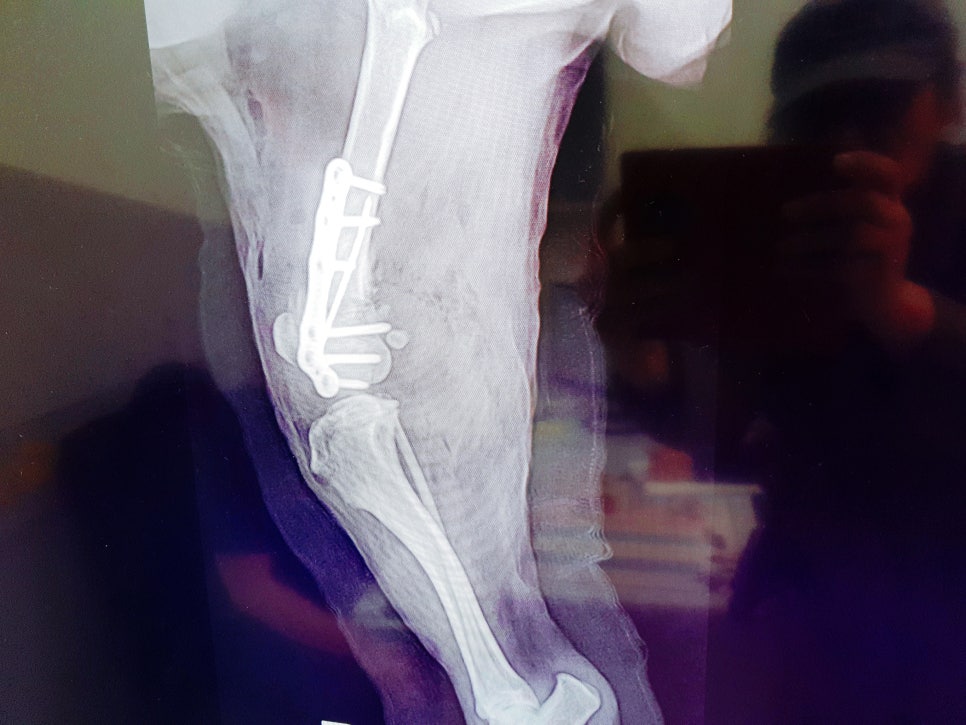

설탕이는 뒷다리에 임플란트로

고정을 해서 평생 임플란트를

심고 살아야 한다고 하더라고요

뒷다리가 어찌나 얇고 말랐던지